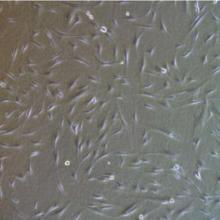

Regeneration: what does it mean and how does it work?